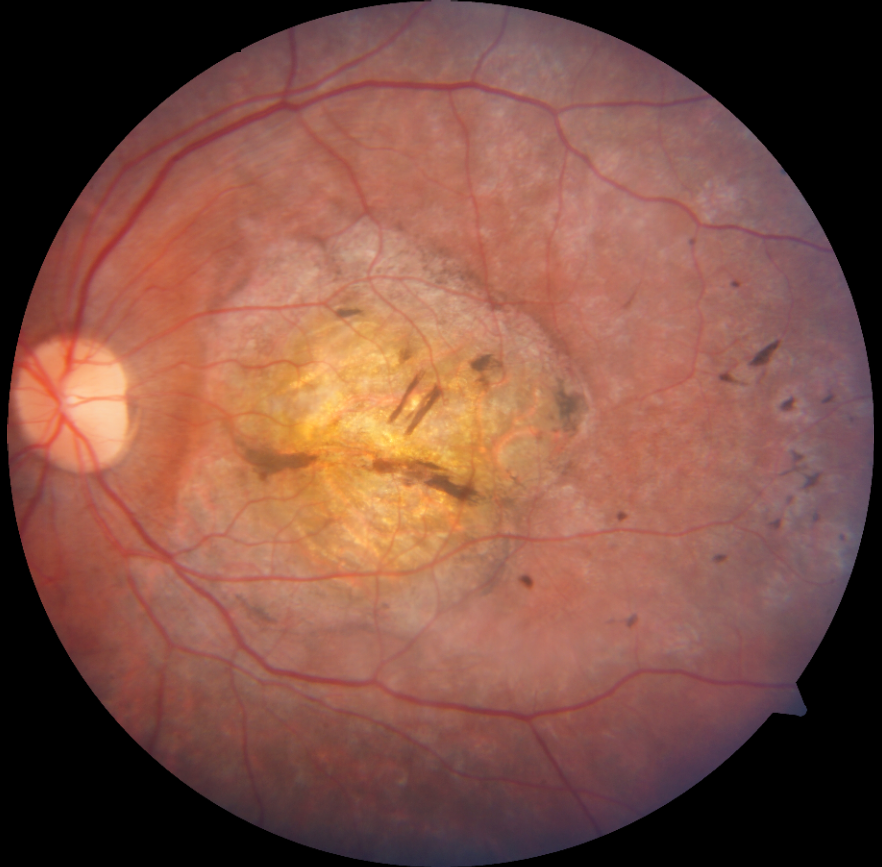

14 yaşındaki erkek hasta bebeklikten bu yana görme kaybı öyküsü ile kliniğimize başvurmuştur. Ailenin tek çocuğudur, anne baba arasında akraba evliliği öyküsü mevcuttur ve her iki gözde görme 1 mps düzeyindedir. Hastanın renkli fundus, FAF ve OCT görüntülerini görmektesiniz. Lütfen cevabınızı aşağıya yazınız.